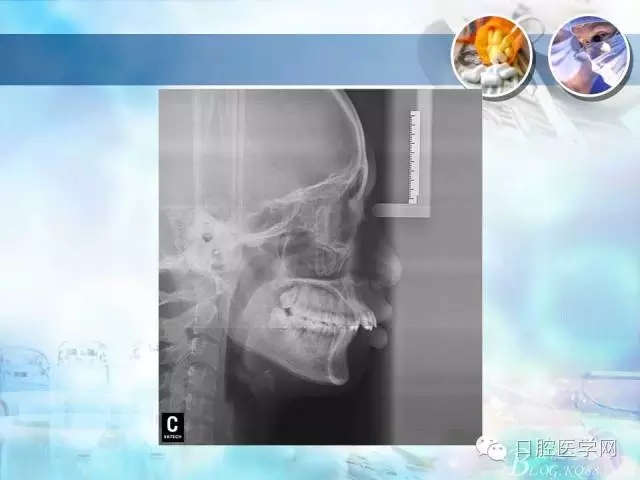

錯(cuò)合畸形中長度不調(diào)的治療